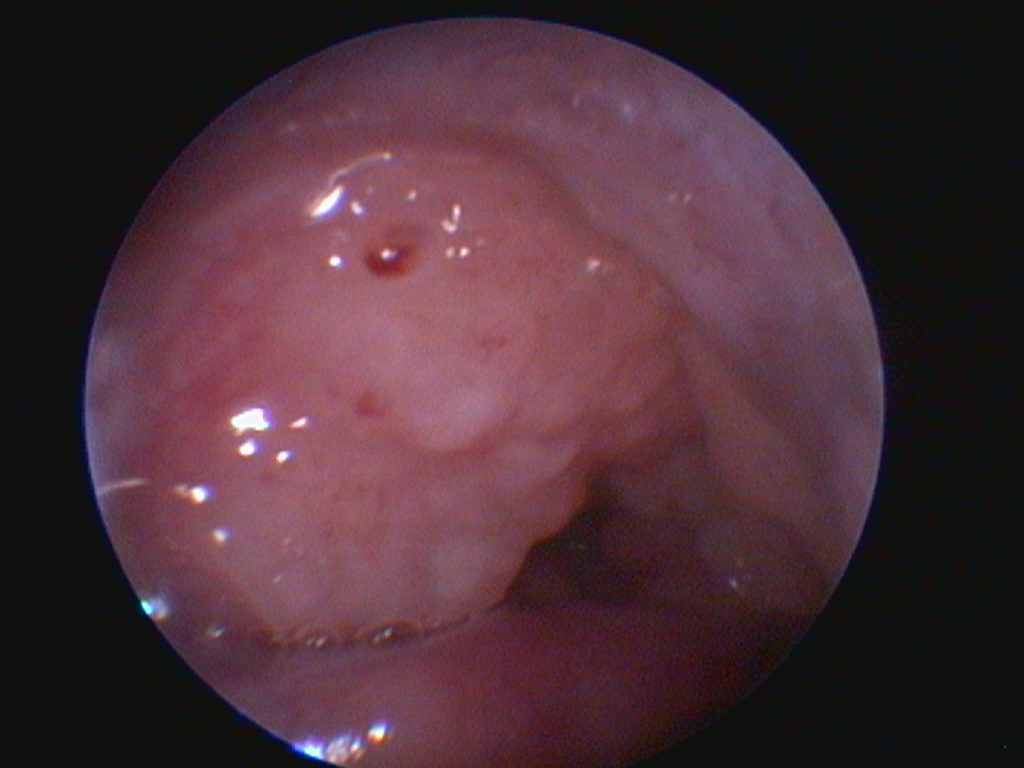

По результатам риноскопии слева носовые ходы были проходимы на всем протяжении, без содержимого в просвете, в ростральной трети на носовой перегородке и дорсальной стенке носового хода были обнаружены множественные объемные образования с шероховатой поверхностью, сглаженными границами, неравномерно окрашенные, с белыми мелкими включениями (фото 3). Результат риноскопии носовых ходов с правой стороны был аналогичным, но на носовой перегородке этих образований было выявлено больше. При проведении биопсии материал из патологической ткани носовой полости и конъюнктивы отбирался с трудом, ткани наощупь были плотными, хрящеобразными, кровотечение было умеренным.